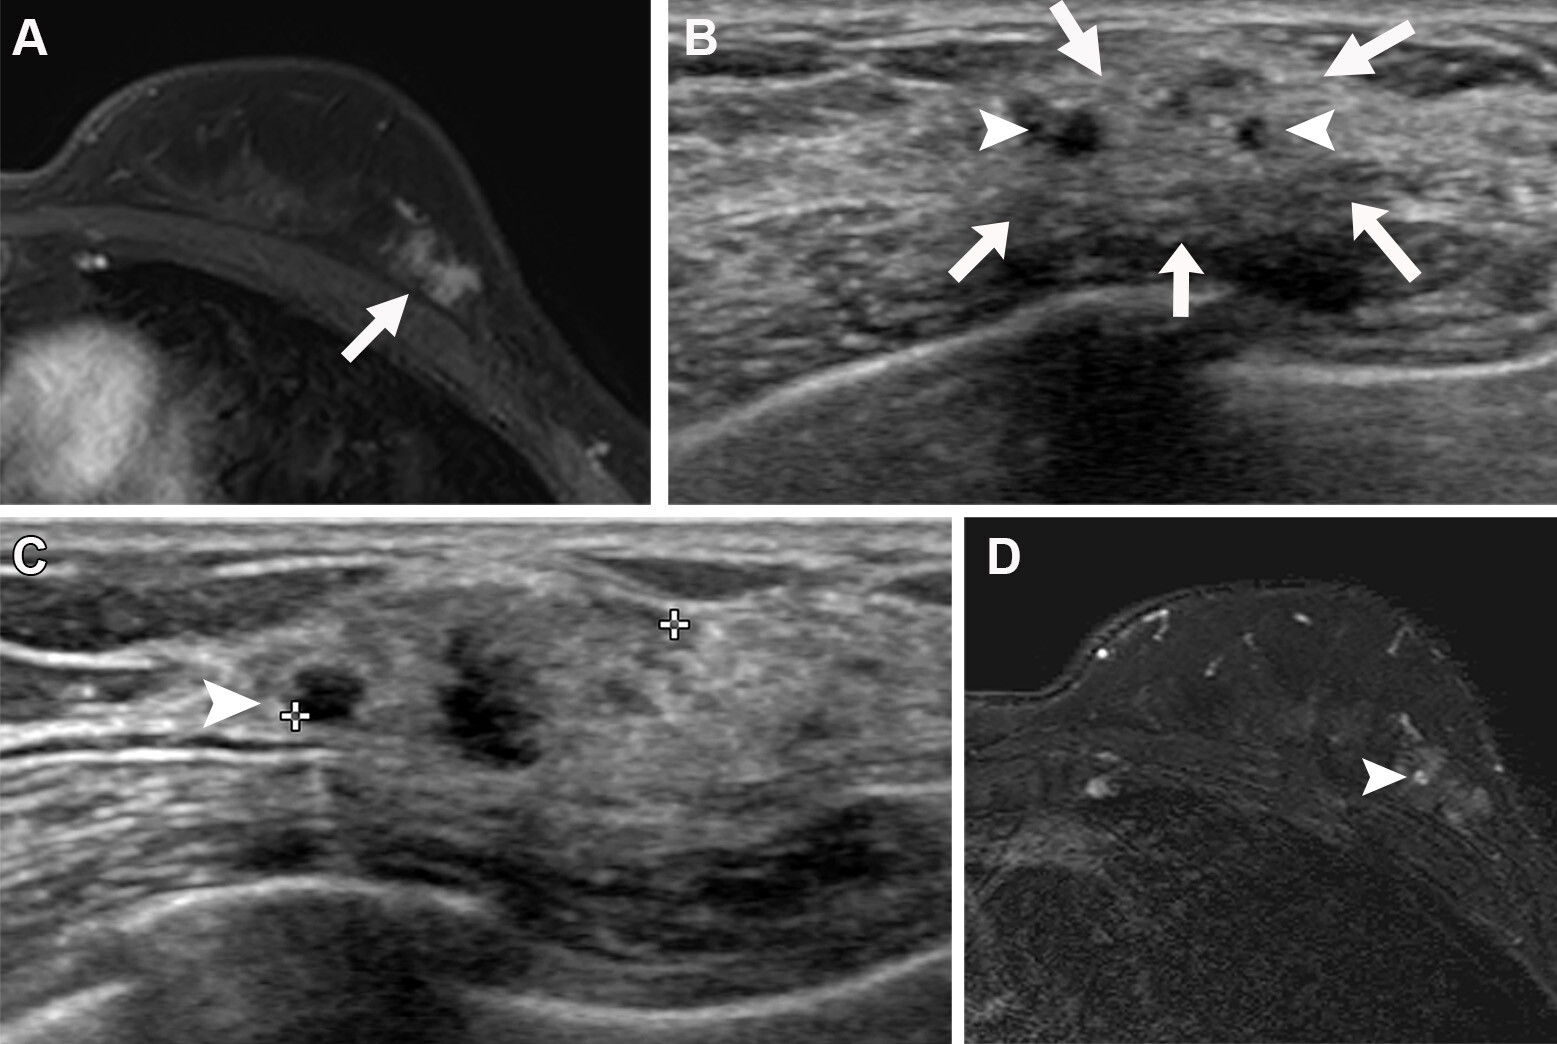

FIGO classification helps categorize uterine fibroids based on their relationship to endometrial and serosal surfaces. Stratification by fibroid type is clinically meaningful since it influences surgical management.

The radiologists achieved moderate overall interobserver agreement (K = 0.461) for FIGO classification. However, agreement varied by subtype. The radiologists achieved substantial agreement for evaluating submucosal fibroids (K = 0.73) and sub-serosal fibroids (K = 0.693). However, they achieved lower agreement for hybrid and intramural fibroids, with K values of 0.387 and 0.33, respectively.

The most common disagreements occurred between FIGO types 2 and 3. This especially went for cases where multiple fibroids distorted the uterine cavity or when fibroids occupied multiple anatomical compartments.